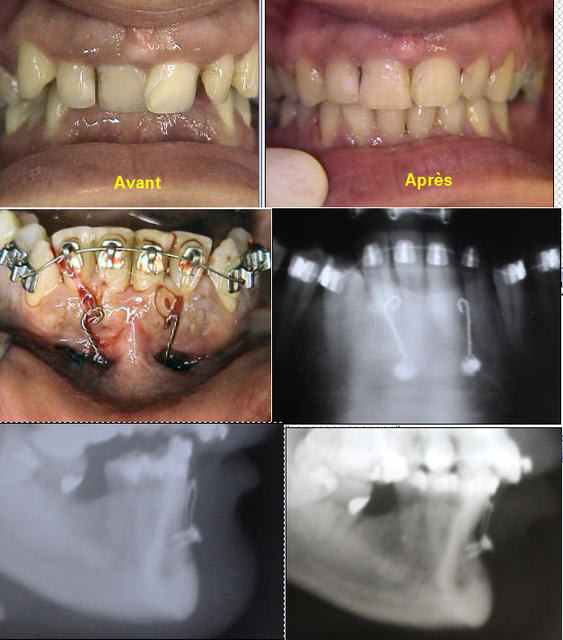

Solène, voici un cas semblable au tien, les images parlent plus qu'un long discours, j'ai commencé la surélévation en réalignant au maximum les milieux (freins incisifs) et en confiant à mon patient un Soulet-Besombes pour classe III, pour l'instant malgré quelques difficultés pour manger, il se trouve bien dans sa nouvelle occlusion, la suite en septembre.

Tout d'abord les photos avant traitement

Et les photos en cours de réalisation

Emma Bravo pour tes photos et l'évolution de ton cas. Peux-tu quantifier l'augmentation de DV du patient ?

J'ai néanmoins le sentiment, en regardant les photos de début de traitement, que le patient a un maintient de la DV postérieurement ( au moins à droite car il a des CCM faces à des CC. Est-ce que l'augmentation de DV a été bien supportée par le patient et sur combien de temps as-tu réalisé la 1ère phase du traitement? Enfin qu'est-ce qu'un Soulet-Besombes ?